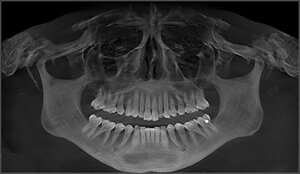

Each patient underwent a medical and dental history, a comprehensive clinical examination, standardized 3D-CBCT imaging, (Figure 1 & Figure 2) to confirm TMJs were stable and well adapted.